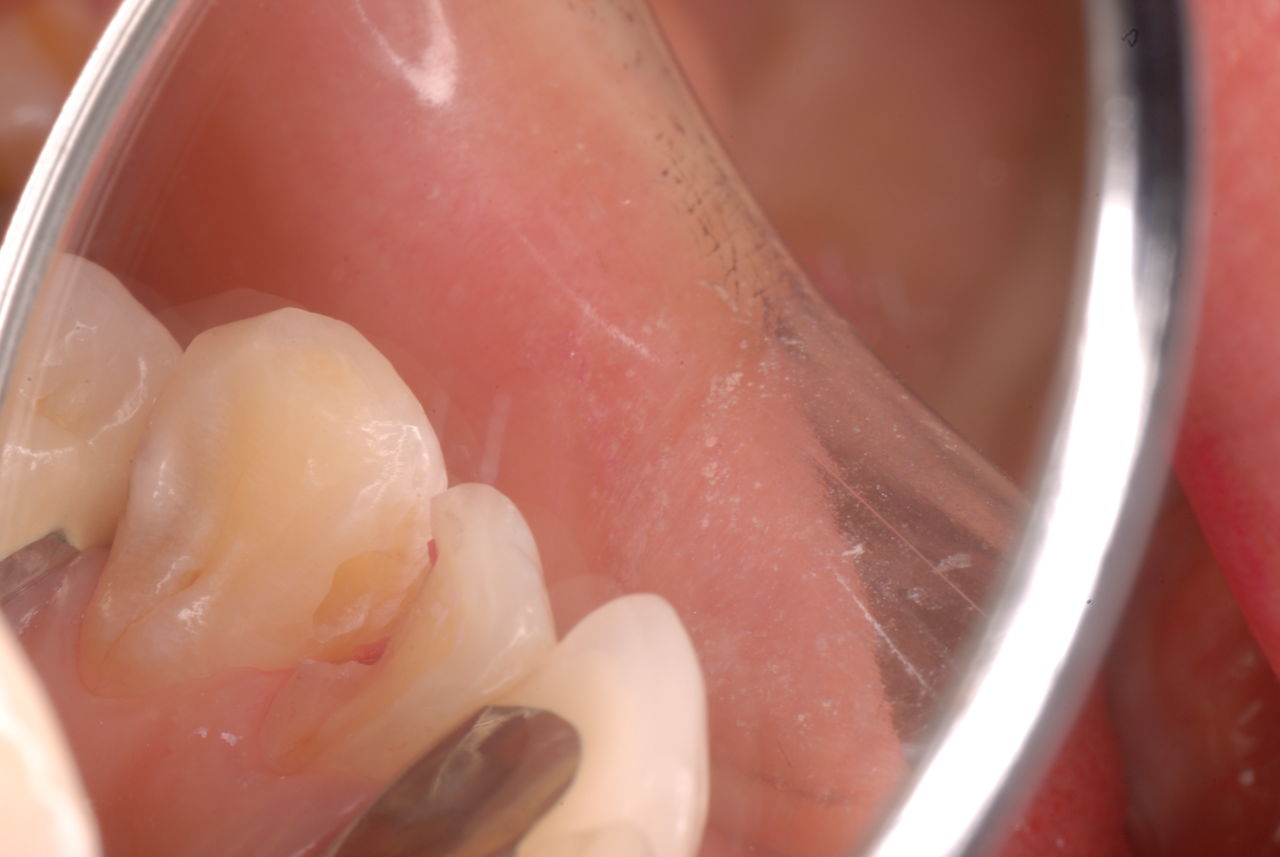

ご自分でやられても歯茎から血が出ないと話をされていましたが、私がブラシを当てると悲惨な状態であることがわかりました。

何故歯が悪くなるのか、歯周病で抜けるのか分からなければ何を入れても歯は悪くなり抜けていくのです。